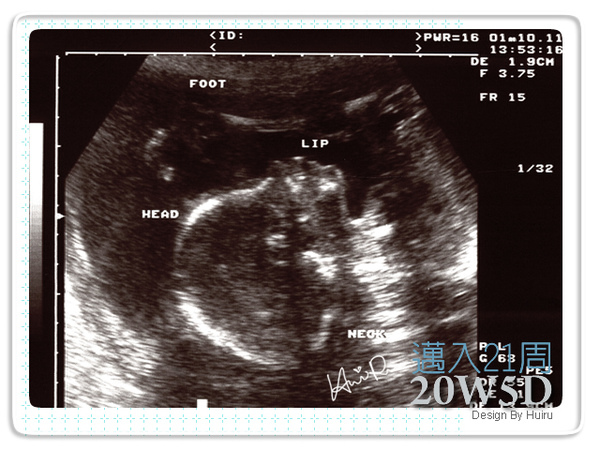

這次的超音波跟之前很不一樣,是由另外的超音波師來負責檢查,每個環節都照得非常地仔細,過程中我也沒問她太多的問題,直到過了幾分鐘後,她開口跟我解釋DD的狀況,包括臍帶、羊水、DD的心臟、胃、脊椎、再次確認性別、五官....等。

五官沒有問題,也沒有兔唇

一邊趙她還會一直笑,因為好正的姿勢她說好好笑喔,好像再練軟骨功,腳竟然在頭的上面;過一會兒又看到好正的舌頭一直動一直動,她就說他在吐舌頭ㄟ,看來醫師比我還開心ㄟ,還細心的幫我標示一些位置。